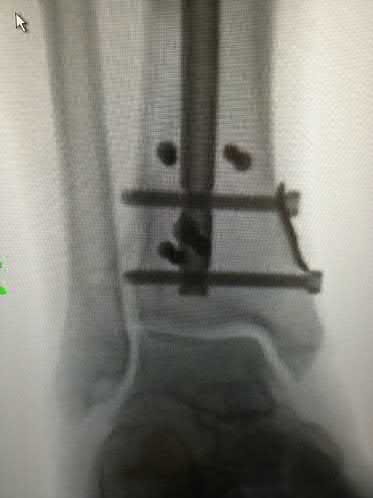

A 25-year-old female is involved in a motor vehicle collision. She presents with the isolated injury seen in Figures A through D. Her leg is swollen but her skin is intact. She has no clinical signs of compartment syndrome. Which of the following treatment options will allow for maintenance of fracture alignment and minimize the risk of soft tissue complications?

The patient presents with a closed distal third metaphyseal-diaphyseal distal tibia fracture with simple intra-articular extension. Immediate intramedullary nailing along with percutaneous fixation of the articular component provides appropriate restoration of length, rotation and alignment and minimizes the risk of wound complication.

Displaced distal third tibia fractures may be associated with simple intraarticular extension. Operative treatment of intra-articular distal tibia fractures has historically been performed with open reduction and internal fixation. Early open reduction and plate fixation of pilon fractures has been associated with high rates of infection and wound complication. In select patterns with simple articular extension, percutaneous screw fixation and medullary nailing may provide appropriate reduction with minimal soft-tissue risk.

Marcus et al. evaluated the outcomes of immediate intramedullary nailing and percutaneous fixation of simple intra-articular distal tibia fractures (AO/OTA 43 C1 and C2). The authors found excellent rates of union and alignment, however caution against broad application of this technique until more rigorous randomized studies can be performed.

Figures A and B demonstrate a distal third tibial shaft fracture with simple intra-articular extension. The axial and coronal CT cuts in Figures C and D further clarify the articular injury. Illustrations A and B demonstrate a comminuted distal third tibial fracture with simple intra-articular extension. Illustrations C and D are fluoroscopic images of the same injury after intramedullary nailing and percutaneous fixation of the articular component.